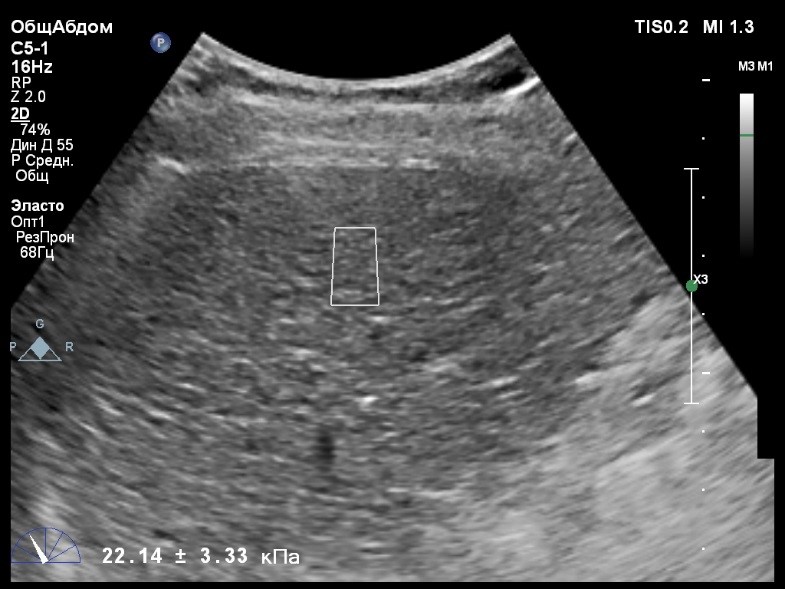

Пациент обратился к доктору с направлением на исследование степени жесткости печени в ноябре 2017 года. Из истории болезни, пациент страдает Гепатитом С с 2002 года. Закончила противовирусное лечение в мае 2017 года. В сентябре 2016 года, с помощью транзиентной эластографии была установлена медиана жесткости печени 45 kPA. На момент настоящего исследования, пациент не принимал пищу на протяжении 4 часов, АСТ, АЛТ не превышают патологических значений. В виду технических сложностей выполнения исследования (узкие межреберные промежутки), для оценки жесткости была выбрана технология компании Philips ElastPQ (точечная эластография) и прибор компании Philips Epiq 7. Исследование было проведено в соответствии с клиническими рекомендациями для ультразвуковых приборов компании Philips. В результате исследования были получены следующие результаты:

| 1 [17.28] kPa | 2 [13.59] kPa | 3 [14.47] kPa |

| 4 [16.71] kPa | 5 [18.48] kPa | 6 [21.20] kPa |

| 7 [21.36] kPa | 8 [15.64] kPa | 9 [19.95] kPa |

| 10 [19.89] kPa | 11 [22.14] kPa | 12 [16.48] kPa |

| 13 [16.41] kPa | 14 [22.02] kPa | |

Стандартное Отклонение [2.75] kPa Медиана Жесткости [17.88] kPa Фактор Качества IQR/Med 9%

Зона интереса расположена на более чем на один сантиметр глубже капсулы, параллельно ходу луча, в середине изображения, в участке печени лишенном артефактов.

Капсула видна как белая линия перпендикулярная ходу ультразвукового луча, исследования производятся приблизительно в одном и том же сегменте печени.

Для интерпретации полученных клинических данных были использованы Рекомендации по проведению эластографии сдвиговой волной для оценки жесткости печени при использовании ультразвуковых аппаратов компании Филипс с примером протокола. Следует отметить достаточно высокую жесткость печени у пациента по данным предыдущих обследований и низкую активность основного заболевания по данным биохимических проб, что является показанием для динамического наблюдения и оценки жесткости печени. Отмечу, что для проведения исследования у данного технически сложного пациента был совершенно обоснованно выбран аппарат экспертного класса. Подготовка пациента соответствовала проводимому исследованию. Представленные слайды проведенного исследования свидетельствуют о правильном техническом исполнении проб, что позволяет заключиться о достоверности полученных измерений. Таким образом, учитывая полученную медиану жесткости на уровне 17,88 кРа (13.59 -22.02 kPa) и уровень стандартных отклонений не превышающих 30%, полагаю, что уровень степени фиброза соответствует стадии F4. Заведующий отделением УЗД МЦ «Асклепий», Глушенко Д. Е.